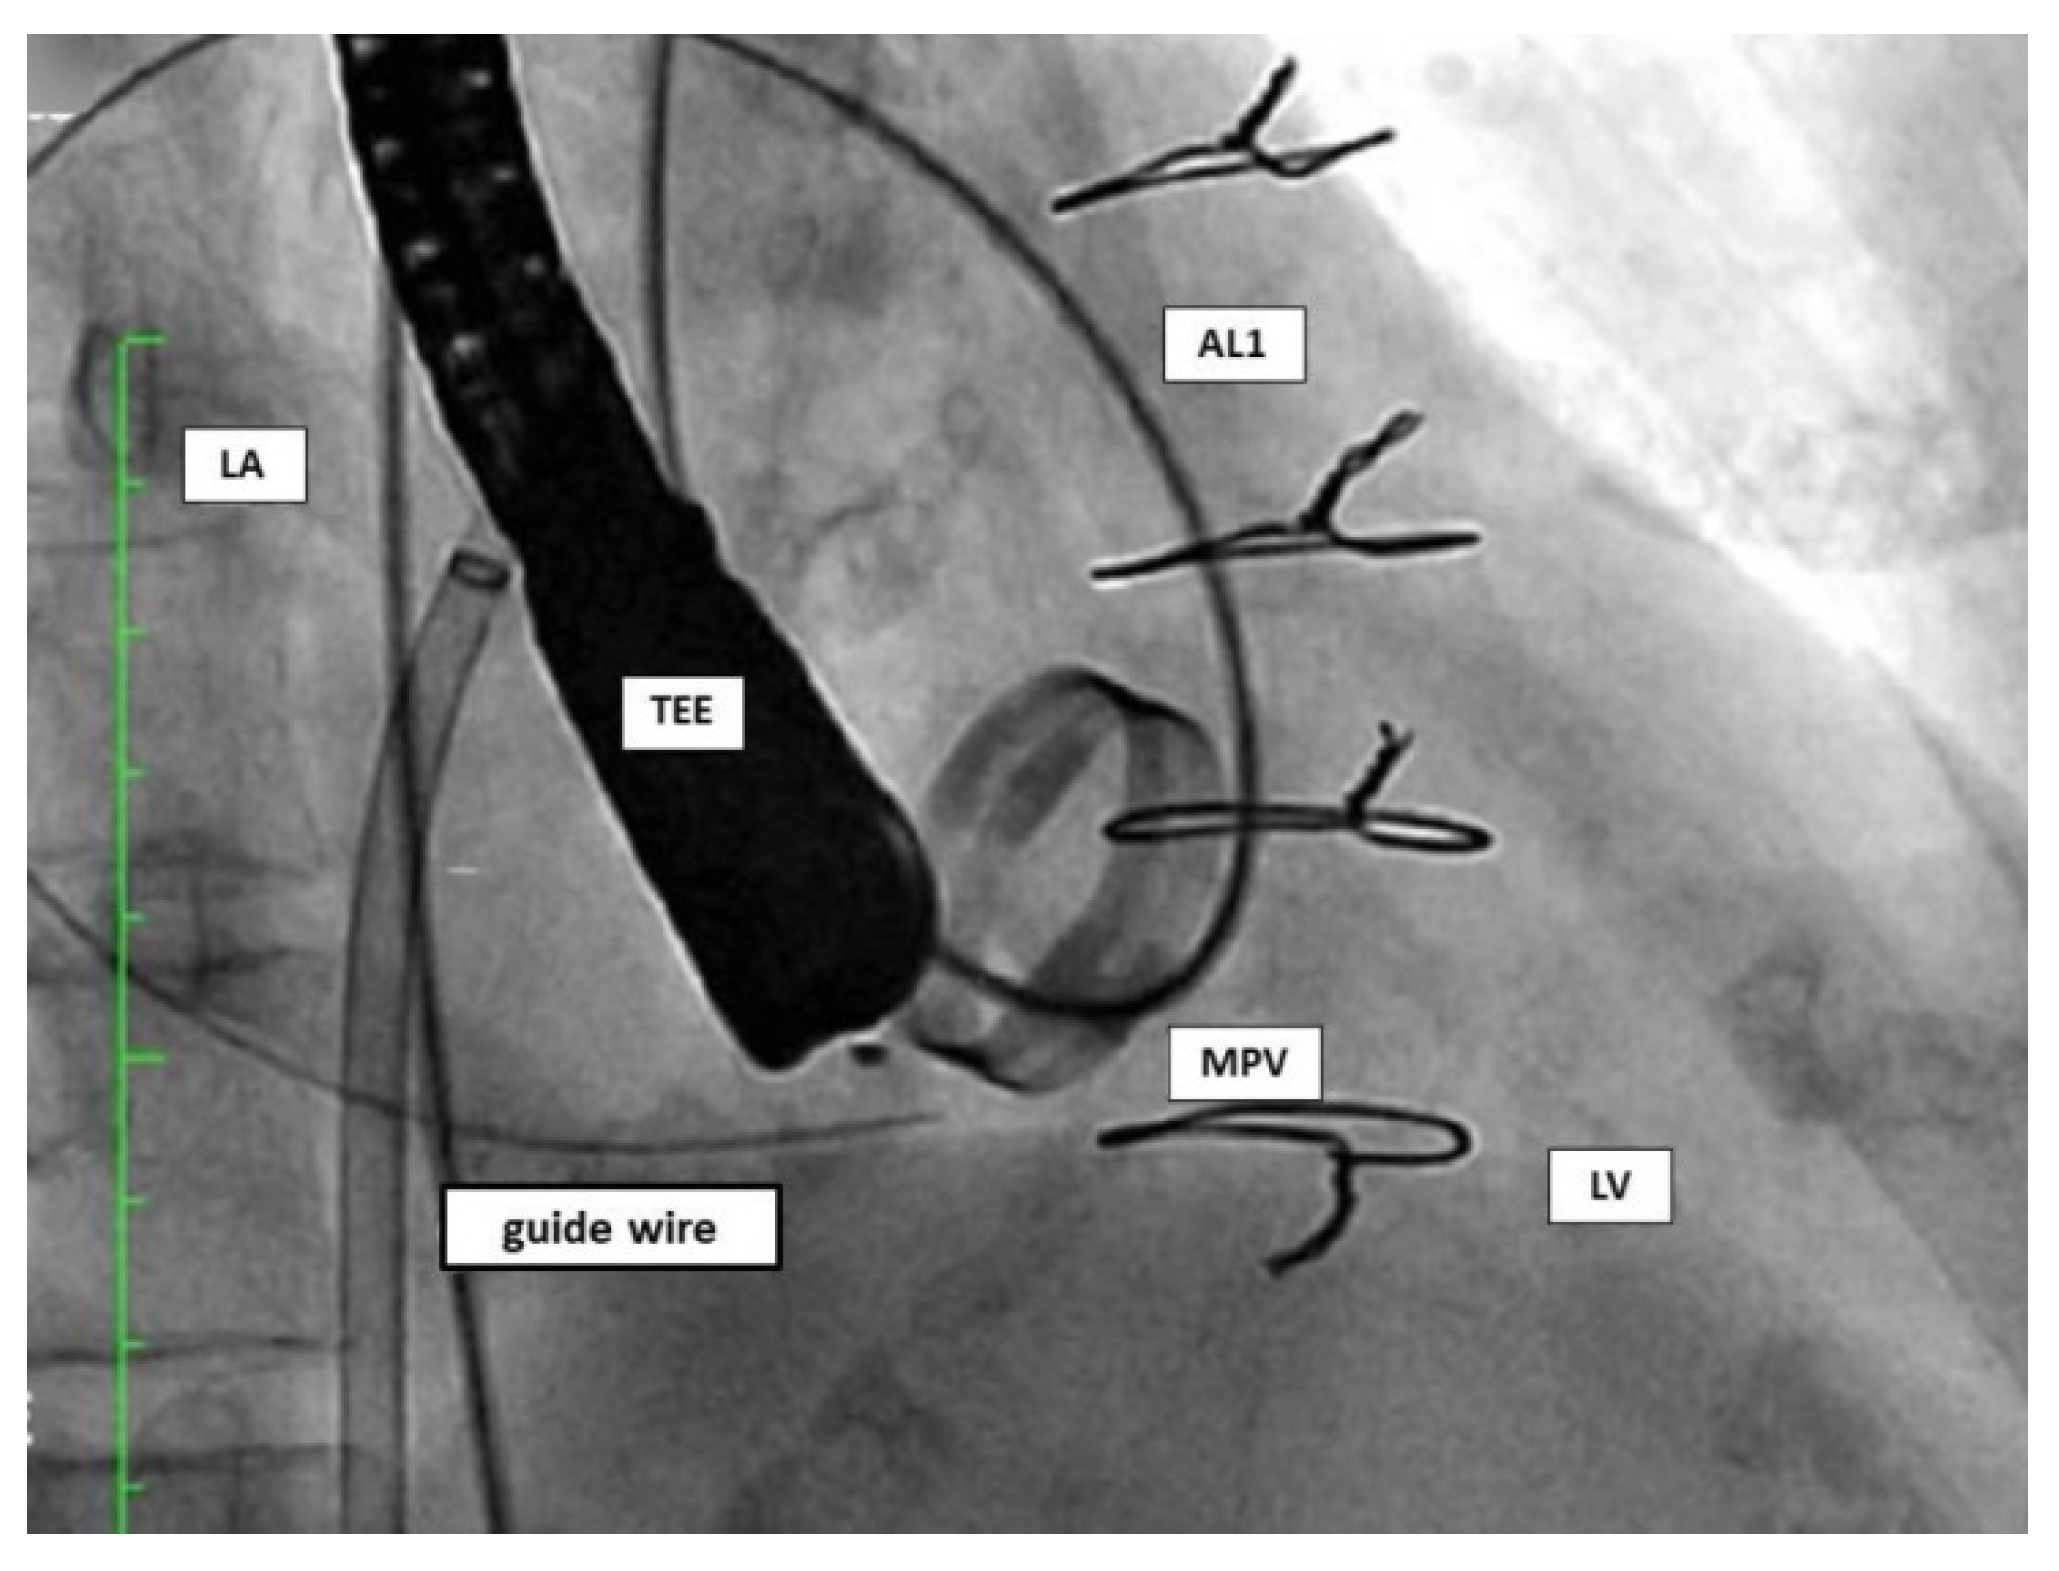

4.3. Procedure

4.3.1. Anterograde Approach

4.3.2. Retrograde Approach